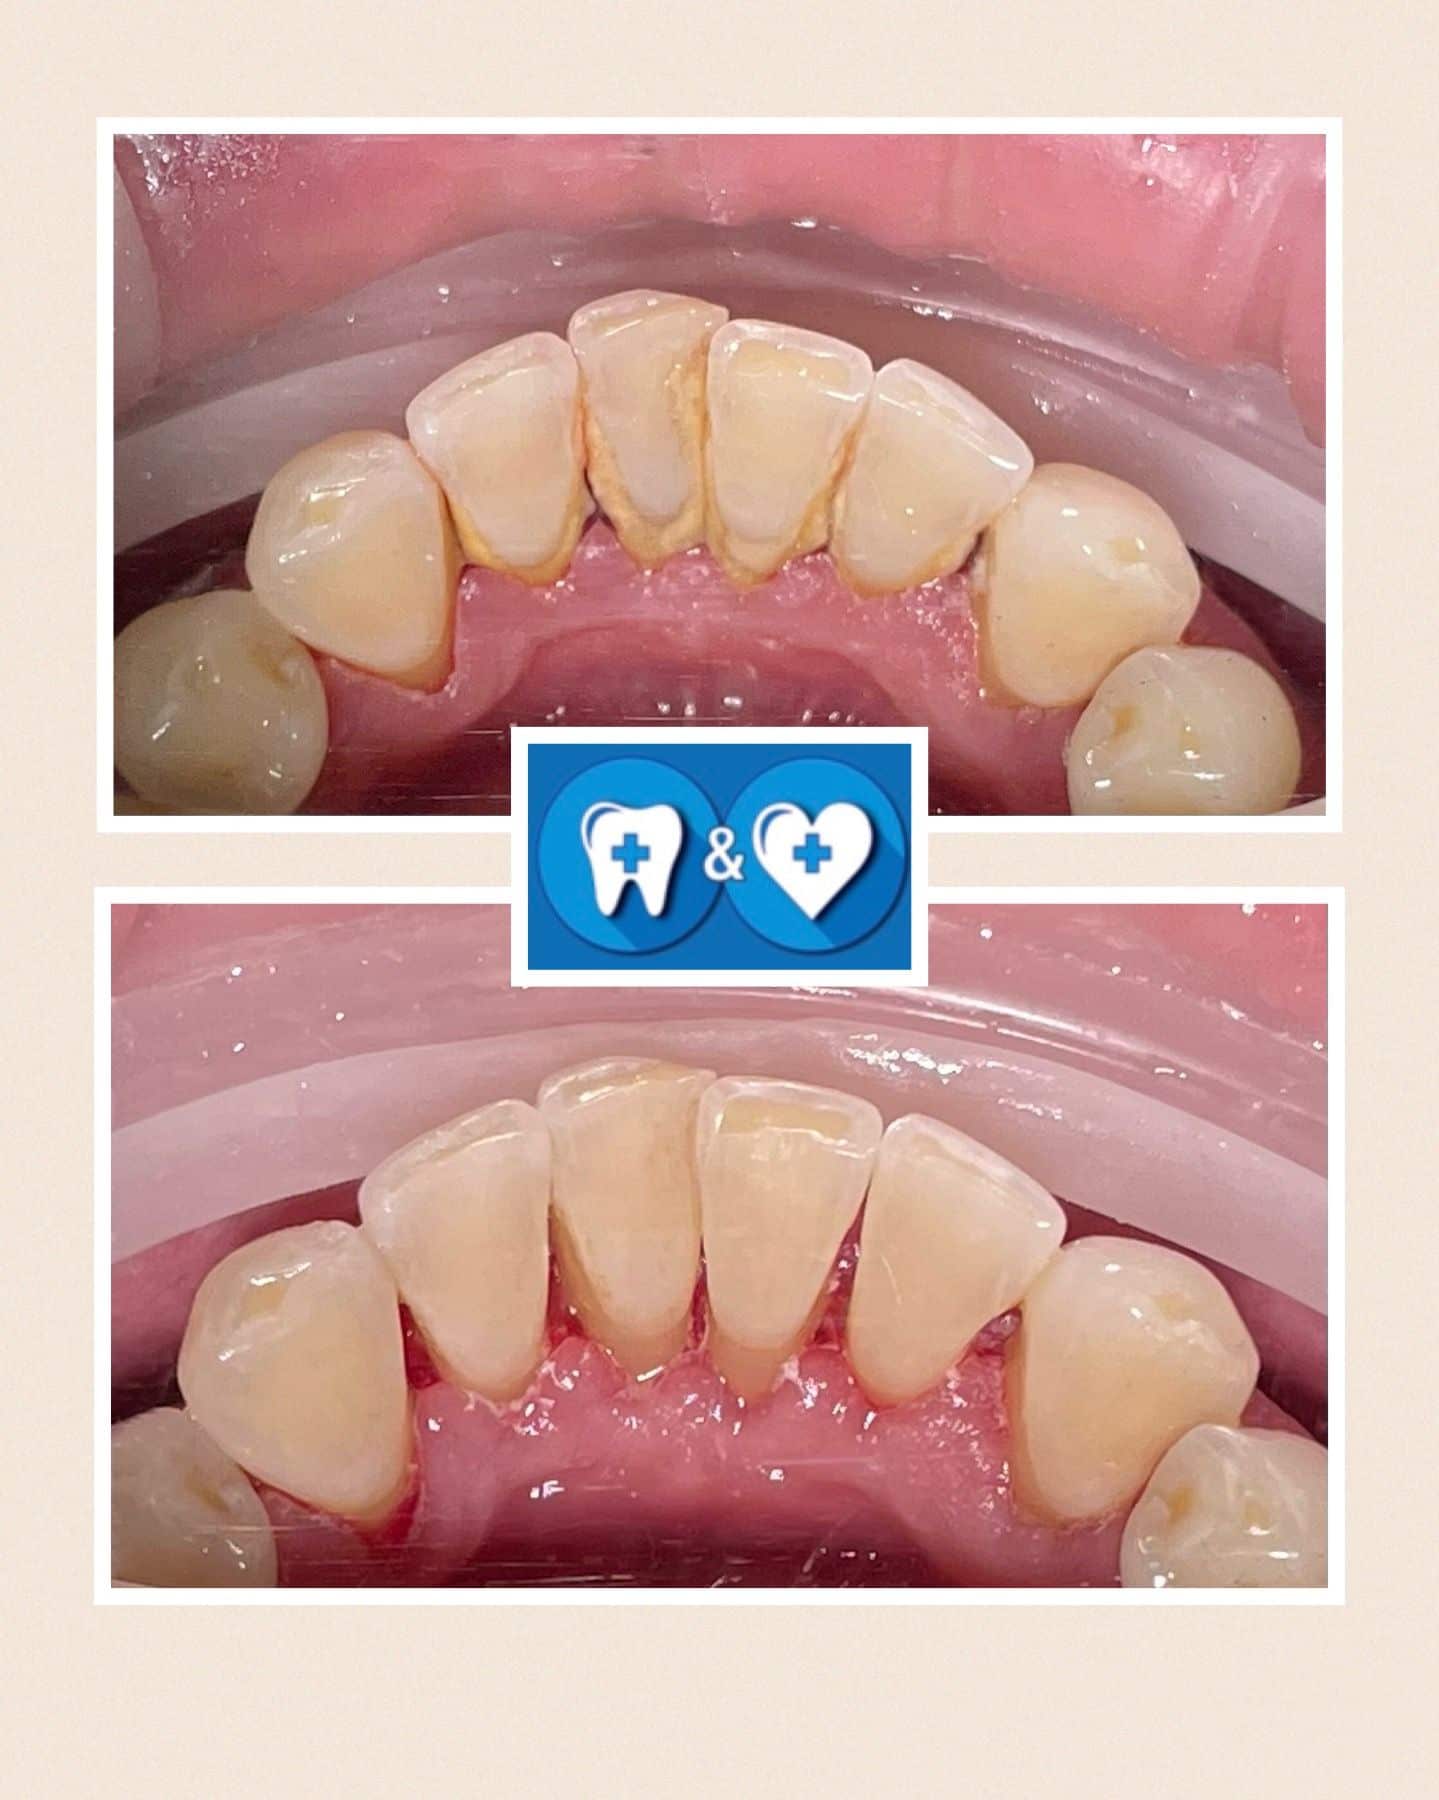

Specialiais instrumentais ir ultragarsiniu skaleriu pašaliname ant dantų susikaupusius akmenis. Su smėliasrove ir perlų soda nuvalome tabako, arbatos, kavos, vyno apnašas.

Dantų poliravimas su soda, E-FLOW technologija leidžia pašalinti atsiradusias pigmentines dėmes!

Po burnos higienos procedūros dantys bus daug gražesni ir baltesni! Ir sveikesni!